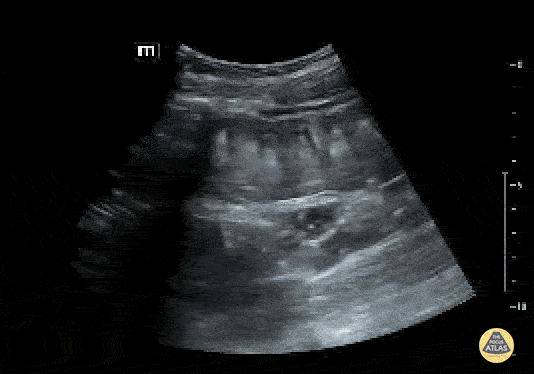

Bowel-GI - To & Fro Peristalsis in Bowel Obstruction

Fecal material can be seen moving forward and backwards through dilated bowels in the patient with a bowel obstruction. Contributed by: Brittany Garza, DO and Saleem Nasseh, MD and Sadie Ellenson, MS4